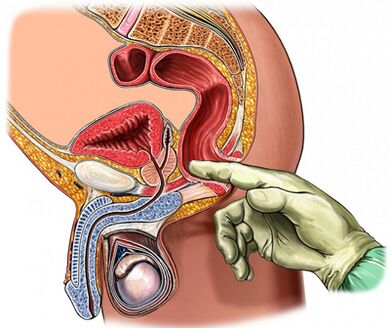

Palpation de la prostate.

La palpation de la prostate est d'une importance primordiale dans le diagnostic de la maladie, qui augmente pendant la période d'exacerbation et diminue pendant la période d'affaissement du processus inflammatoire. Dans la prostatite chronique, pendant la période d'exacerbation, la glande devient enflammée et douloureuse.

La cohérence de l'organe peut être différente: les zones d'adoucissement et de durcissement sont palpées et les zones de rétraction sont déterminées. Grâce à la palpation, il est possible d'évaluer la forme de la glande, l'état des tubercules séminaux et les tissus environnants.

Le processus d'examen numérique transrectal est combiné avec la collection de sécrétions glandulaires. Parfois, il est nécessaire d'obtenir la sécrétion de chaque lobe séparément.